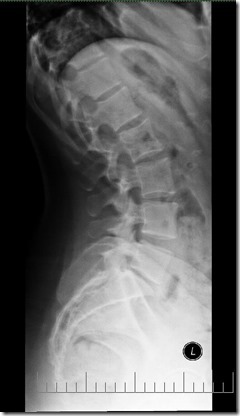

- I had been having some sciatic pain over the past year, and things just didn’t feel right. I had an xray to see what’s up. I thought it was a herniated disc (and I actually still do), but it’s being caused by an extreme curve that is pinching all my nerves there!

The left image is my lower spine. And the right image is what it’s supposed to look like. Yikes! Luckily physical therapy has been going well. I’m optimistic.